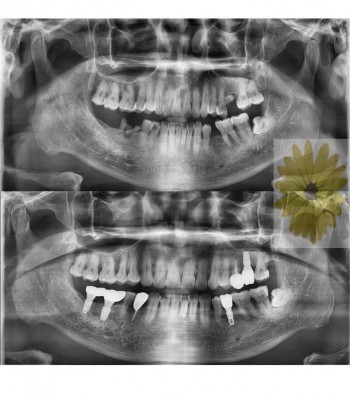

치료전후사진

민들레치과 치료 전후 사례

민들레치과 치료 전후사례